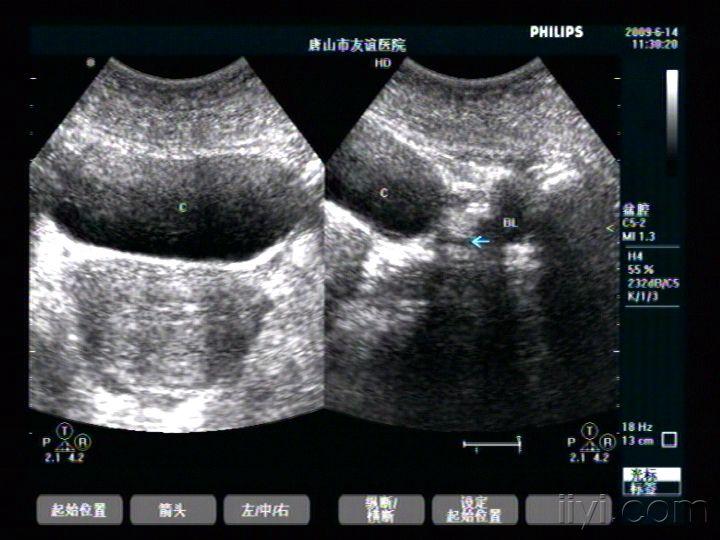

膀胱憩室两例 - 超声医学讨论版 - 爱爱医医学论坛

图片尺寸768x576